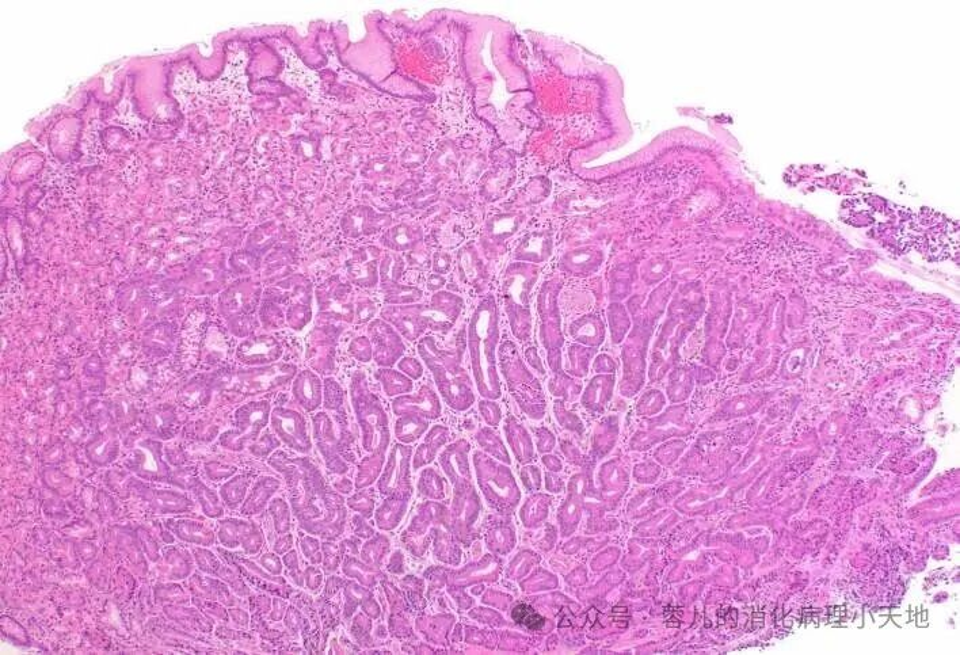

胃小凹发育不良,胞质嗜酸性,核增大、染色质增多,轮廓不规则

组织学特征:胞质嗜酸性,核增大、染色质增多,轮廓不规则

好发部位:胃体部胃泌酸黏膜表面